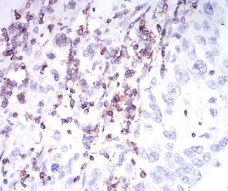

IHC    1/200 - 1/1000